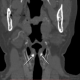

Оссификация черпаловидных хрящей, КТ.

Впервые встретилось, решила поделиться. Нормальный вариант практически с полным двусторонним обызвествлением (=оссификацией=склерозом). Случайная находка при КТ сосудов шеи.